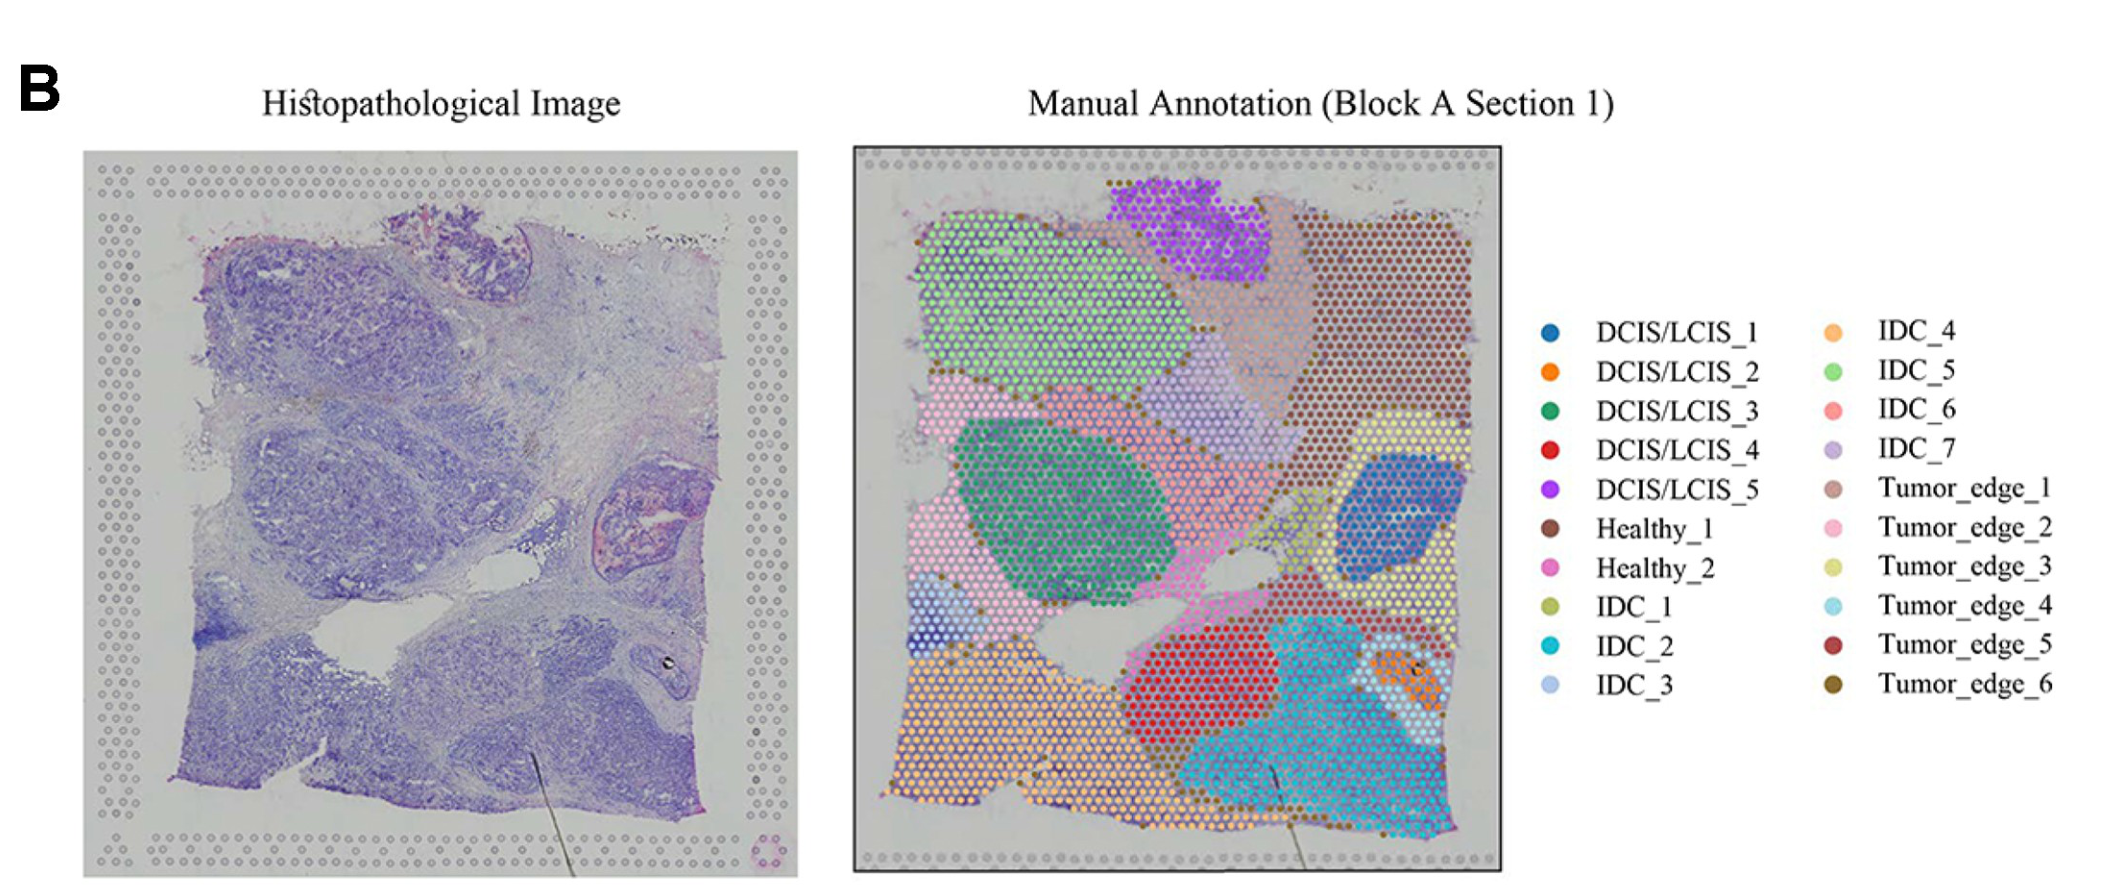

Modality

Sequencing-based